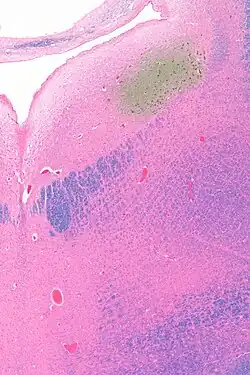

The locus coeruleus (LC) is located in the posterior area of the rostral pons in the lateral floor of the fourth ventricle. It is composed of mostly medium-size neurons. Melanin granules inside the neurons contribute to its blue colour. Thus, it is also known as the blue nucleus, or the nucleus pigmentosus pontis (heavily pigmented pontine nucleus).[5] The neuromelanin is formed by the polymerization of norepinephrine and is analogous to the black dopamine-based neuromelanin in the substantia nigra.

The locus coeruleus is affected in many forms of neurodegenerative diseases: genetic and idiopathic Parkinson's disease, progressive supranuclear palsy, Pick's disease, and Alzheimer's disease. It is also affected in Down syndrome.[29] For example, there is up to 80% loss of locus coeruleus neurons in Alzheimer's disease,[30] Mouse models of Alzheimer's disease show accelerated progression after chemical destruction of the locus coeruleus.[31] Neurofibrillary tangles, a primary biomarker of Alzheimer's disease, may be found in the locus coeruleus decades before any clinical symptoms.[32] The norepinephrine from locus coeruleus cells in addition to its neurotransmitter role locally diffuses from "varicosities". As such it provides an endogenous anti-inflammatory agent in the microenvironment around the neurons, glial cells, and blood vessels in the neocortex and hippocampus.[18] It has been shown that norepinephrine stimulates mouse microglia to suppress Aβ-induced production of cytokines and promotes phagocytosis of Aβ.[18] This suggests that degeneration of the locus coeruleus might be responsible for increased Aβ deposition in AD brains.[18] Degeneration of pigmented neurons in this region in Alzheimer's and Parkinson's disease can be visualized in vivo with Neuromelanin MRI.[33] Since the marked degeneration of locus coeruleus, and the neuroprotective properties of noradrenaline, Ian Robertson proposed the "Noradrenergic Theory of Cognitive Reserve" [34] which postulates that the upregulation of the locus coeruleus-noradrenergic system throughout the lifespan may enhance cognitive stimulation contributing to cognitive reserve preventing from neurodegeneration. Evidence appear to support this theory reporting the locus coeruleus integrity primarily responsible of biological brain maintenance,[35][36][37] including brain clearance,[38] cognitive efficiency, and reduced neuropathological burden.[35][39][40][41]